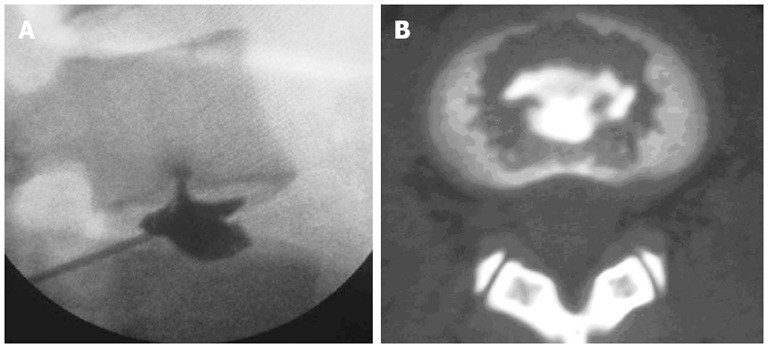

我们将椎间盘造影和椎间盘造影后的CT扫描结合起来,以评估IED患者的终板破裂程度。 破坏度分为4个等级:

0级(无破坏),

1级(造影剂通过撕裂流入软骨终板),

2级(造影剂流入骨终板) ,

3级(造影剂在终板下方流入椎骨松质骨,显示局部分散)

4级(造影剂在松质骨中广泛分散)。

在这组IED患者中,所有显示出一致的疼痛反应的椎间盘均比3级更为严重的终板破裂,这与终板上的血管和神经分布相一致。